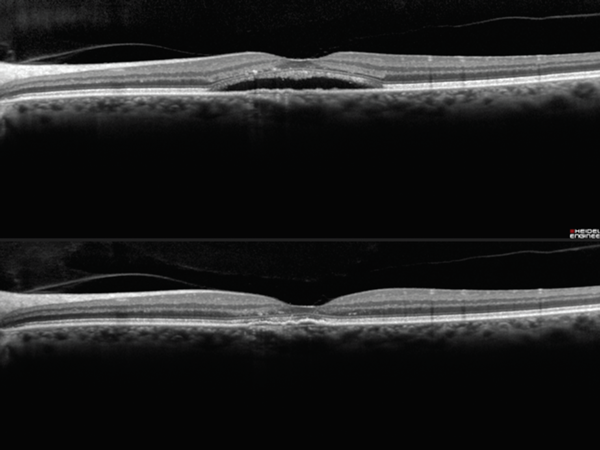

Managing recurrent retinal detachments without PVR